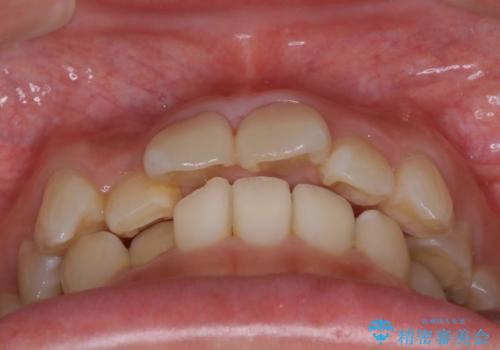

- 20代女性

- 上顎の両側第1小臼歯抜歯による抜歯矯正を計画した。

上顎の抜歯により上の前歯の位置を大幅に後ろに下げることができます。

奥歯の位置関係など、様々な要素を加味し、適応を判断する必要があります。